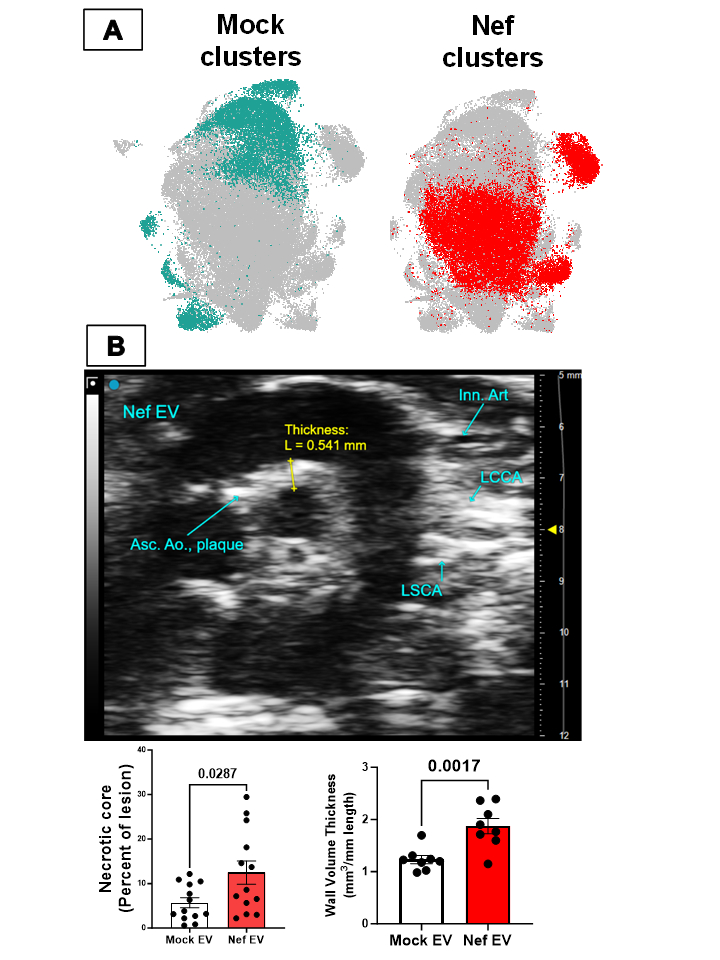

Methods and Results: Macrophage heterogeneity was characterized in human primary macrophages (50,931 cells; 4 donors) stimulated with EVs engineered to contain HIV-Nef by simultaneous scRNAseq and scATACseq. Among 16 clusters (Fig.1A), two inflammatory Nef dominant clusters were characterized using gene set enrichment analysis. Gene regulatory network analysis of scRNAseq (pySCENIC) and transcription factor footprinting analysis of sc-ATACseq (ChromVar) suggest elevated NFκB activation in these clusters. Whole cell and sub-cellular compartmentalized proteomics of nucleus, cytosol, cell surface and secreted EVs indicate changes in immune response related biological pathways. Network analysis of our multi-omics data predicts Bruton Tyrosine Kinase (Btk) signaling as a potential contributor to Nef induced macrophage dysregulation. Pathway enrichment analysis of these multiomics dataset suggest Nef influences atheroprotective efferocytosis through the Btk-NFκB signaling axis. Spectral flow cytometry, high content imaging and multiplexed qPCR showed reduction in key effector of efferocytosis, MerTK. Btk inhibition using siRNA, reversible and irreversible Btk inhibitors restored MerTK expression and rescued efferocytosis. Importantly, CRISPRa based overexpression of MerTK in human primary macrophages rescued Nef impaired efferocytosis. Injection of HIV-Nef EVs into male and female C57BL6/J mice impaired efferocytosis of peritoneal and bone marrow derived macrophages which was rescued with Btk inhibition in vivo. Critically, injection of HIV-Nef EV into male and female Ldlr-/- enhanced atherogenesis with larger aortic wall thickness and necrotic core (Fig.1B).